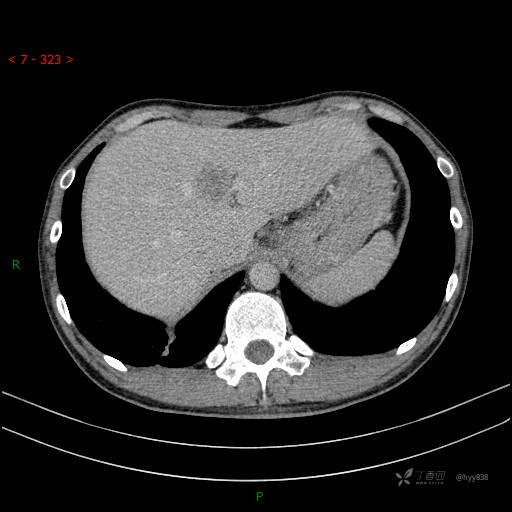

胸部CT平扫

增强动脉期

静脉期